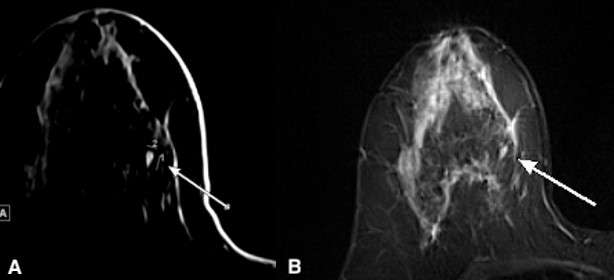

MRI is not necessary for the diagnosis of fibroadenomas. However, small fibroadenomas are often incidentally noted on MRI. Imaging features include T2 hyperintensity and homogenous enhancement with or without non-enhancing T1 hypointense fibrous septae.5